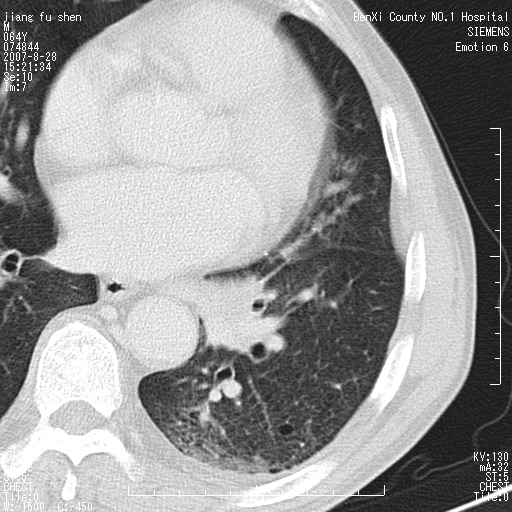

男、64、咳嗽、发烧一周、左肺呼吸音稍弱。既往肺结核,右手结核。

本次扫描患者未带原片,左肺下叶发现病灶。左肺上叶空洞,5组淋巴结肿大,1cm左右。

追问病史三月份ct扫描左肺上叶空洞,医大诊断肺结核。

平扫20-33hu

增强31-33hu

1分半44-52

2分55-67

左肺下叶前内基底段支气管明显偏心性狭窄,周围分叶状肿块,伴有阻塞性肺炎,支持肺癌可能性大。

考虑左肺中央型肺癌并阻塞性肺炎

病灶边缘可见多量较长棘影及纤维条索状影,除外病灶边缘较光整,病灶有分叶表现,但多表现为较浅分叶,且向周围伸出之叶多呈尖角改变,且边缘较光整,病灶增强呈中度延时增强,且早期及中期仅轻度增强,结合患者病史,多考虑继发型肺结核,炎性增殖灶形成,不除外肺癌